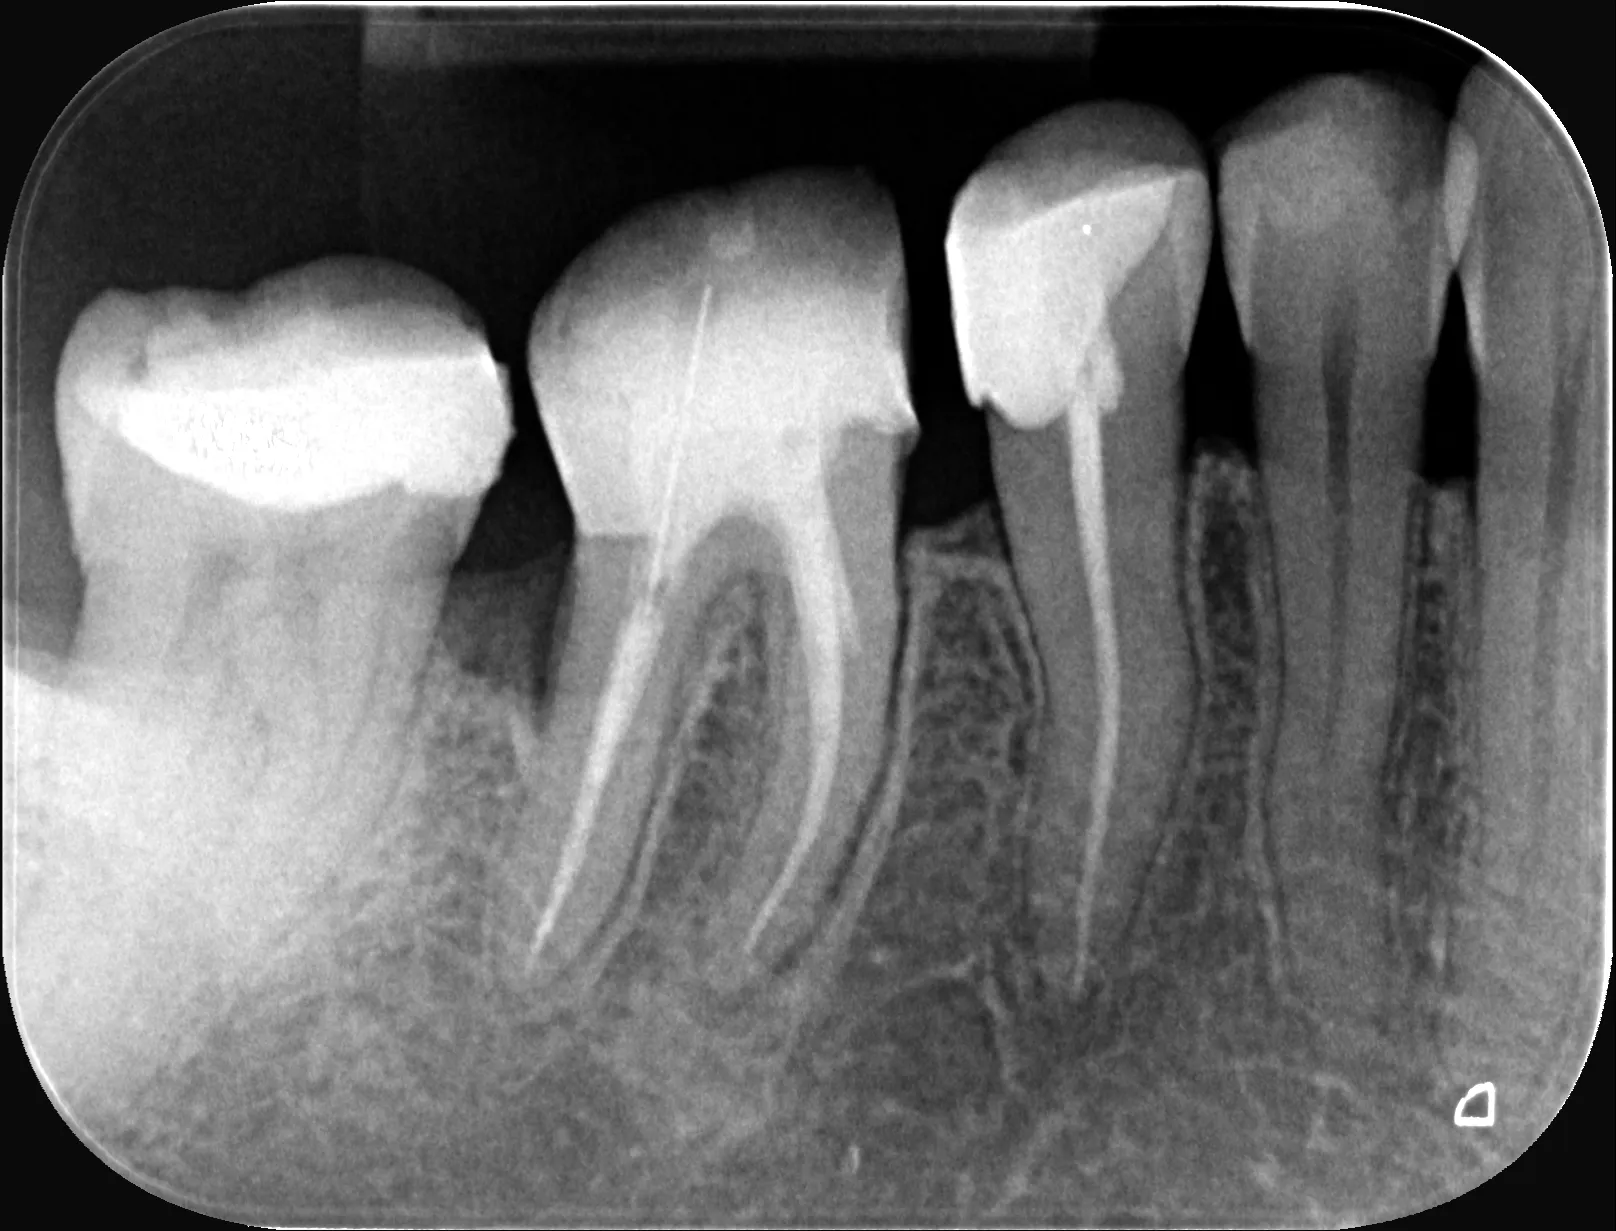

1 – Radiografie initială

14 – Radiografia de control imediat după finalizarea tratamentului endodontic